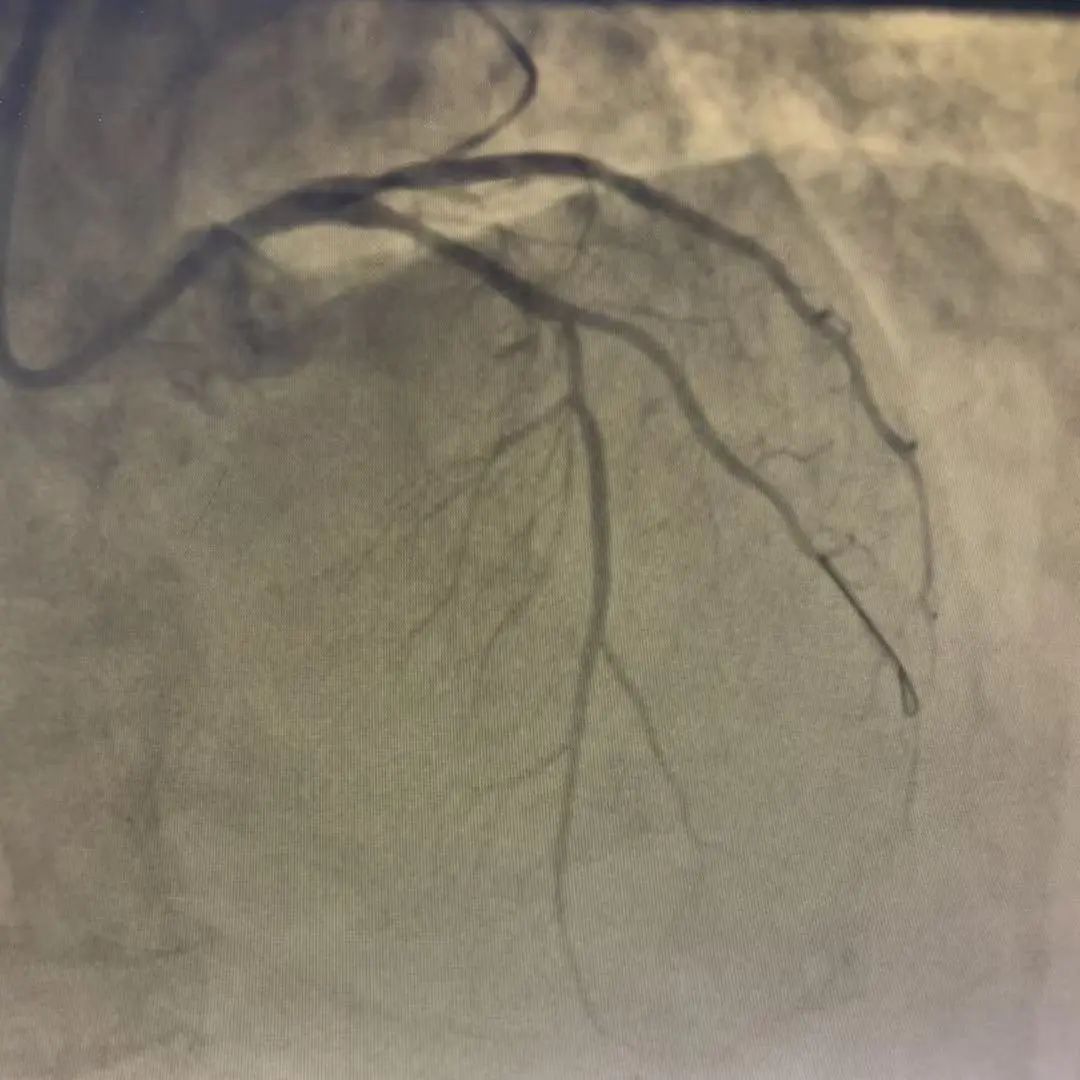

冠脉处置后造影

在心脏随时停跳的极端风险下,赵永富主任及王崇权主任操作导丝精准通过左主干到前降支植入支架一枚,闭塞的“生命主干道”轰然重启,血流恢复,手术全程如履薄冰却一气呵成,整个过程仅用了不到30分钟。由于抢救及时,患者被成功从死亡边缘拉回!